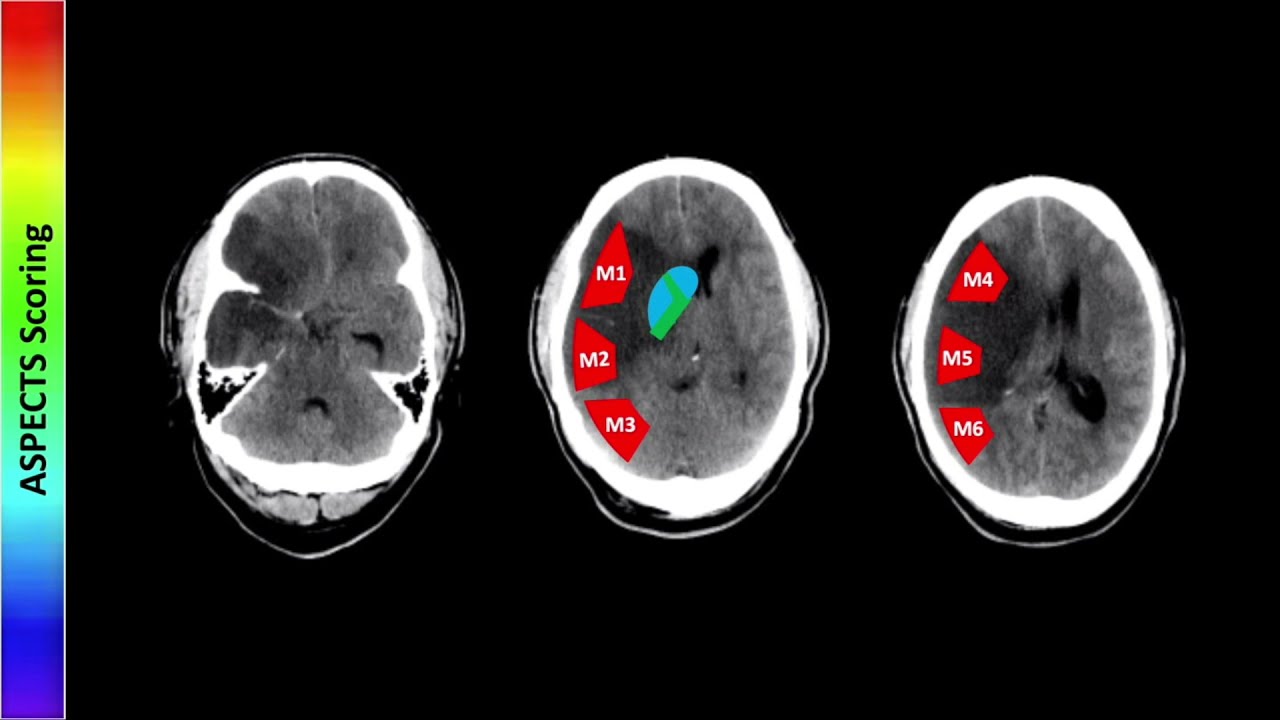

the on the right here we see the white arrows pointing to two areas of stenosis in the coronary arteries two areas that show that dye is kind of cut off is kind of blank for a moment indicating that there's not much blood there's not much fluid passing through the arteries at the point that the arrow is indicating and lastly we have cardiac CT CT is computed tomography and cardiac is obviously computed tomography of the heart which is a more complicated x-ray it's not quite as simple as a normal chest x-ray it's a series of x-rays

that are that are put together by a computer to produce an image and can also be used to produce a three-dimensional image cardiac CT is best to assess the extent of coronary stenosis so we can identify coordinate coronary stenosis best using cardiac catheterization we can we can assess the extent of stenosis we can get a higher resolution picture and see just how bad that artery is being as being clogged up using cardiac CT cardiac CT is also good to look at the thoracic aorta so if we have any kind of a or two problems such

as an aortic dissection cardiac CT can identify that the benefit of cardiac CT is that it's less invasive than catheterization you're not actually putting anything into the body and you can also produce a three-dimensional model which is something that catheterization cannot do and the drawbacks of CT are a pretty intense radiation exposure more so than check stray chest x-rays and more so than MRIs and of course to get some some pretty images you usually have to use contrast that can damage the kidneys so that's all we have for these imaging modalities of the heart I